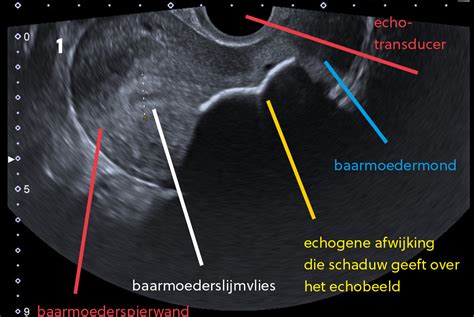

Echo's

Het is een bijzonder moment om naast een positieve zwangerschapstest, de toekomstige baby in beeld te zien! In de zwangerschap kunt u voor verschillende echo's kiezen. Maak een afspraak voor uw echo bij Verloskundig centrum de Poort, waar wij kwalitatief hoogwaardige echo's leveren.